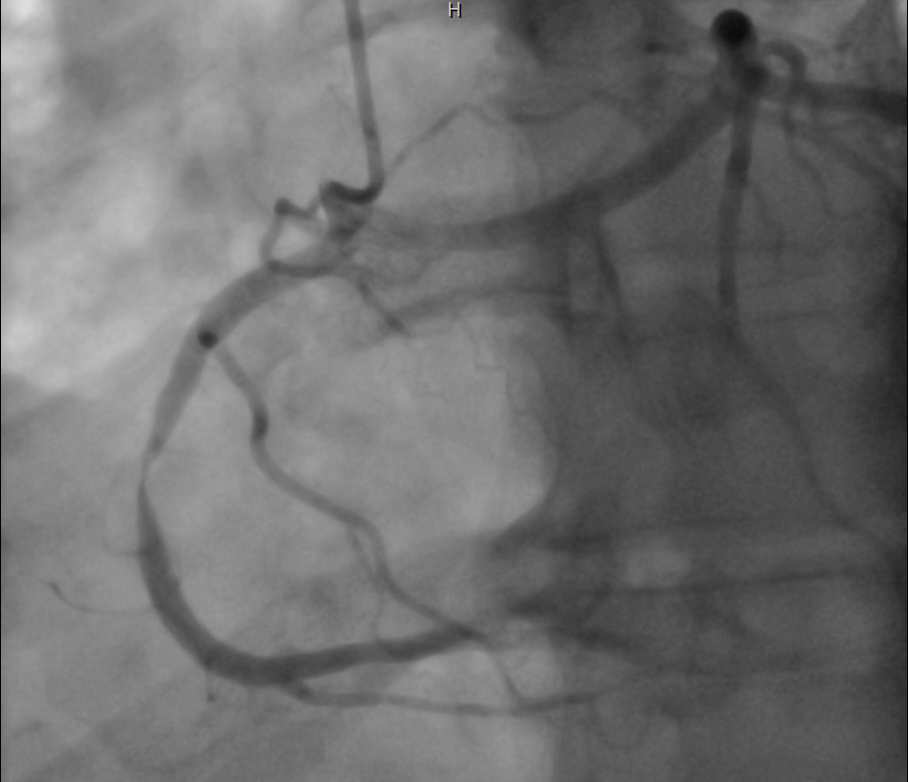

Coronary angiography was performed through right radial approach using 5F TIG catheter. Left coronary sinus contrast injection failed to show any coronary artery origin despite multiple attempts. Right coronary sinus injection showed a coronary artery arising from right coronary cusp as a single trunk which divides into RCA and left system. Left system further divides into LAD and LCX. Mid RCA showed a very tight concentric severe stenosis. Left system was devoid of any significant disease.

Percutaneous Coronary Intervention (PCI) of mid RCA: Common coronary trunk ostium was engaged with a 6F JR4.0 guiding catheter with meticulous care to prevent any ostial injury. Mid RCA lesion crossed with a 0.014¡± BMW wire. Predilated the lesion with 2.5x12mm semi compliant balloon. Stenting of the lesion was done using a DES (3.5x23mm) with final good result. A cardiac CT was done following PCI which confirmed the angiographic findings and found normal subpulmonic non-malignant course of left branch vessel (Lipton's class R II A).